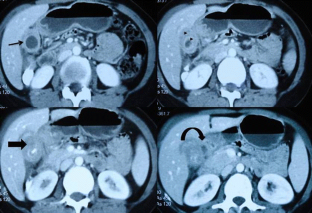

Of the 566 patients with GB mass and suspected GBC, 239 were found to be inoperable on preoperative workup and 129 patients had unresectable disease on staging laparoscopy/laparotomy. Of the 198 with resectable disease, 31 were reported as XGC on final histopathology (Group A), while 167 were GBC (Group B). Of these 31 patients, six with an intraoperative suspicion of benign pathology underwent cholecystectomy with segments IVb and V resection, and frozen section histopathology. Twenty-five underwent radical cholecystectomy, with (n = 10) or without (n = 15) adjacent organ resection. In comparison, anorexia and weight loss were significantly more in Group B (p = 0.001 and <0.001). Intraoperatively, empyema and associated gallstones were more common in Group A (p = 0.011 and <0.001). On computed tomography (CT) of the abdomen, continuous mucosal line enhancement and intramural hypodense bands were significantly more in Group A (p < 0.001 and 0.025). While CT abdomen revealed one or more features suggestive of XGC in 64.5 % (20/31) of patients in Group A, 11(35.5 %) did not have any findings suggestive of XGC on imaging.

Mass-forming XGC mimics GBC, making preoperative and intraoperative distinction difficult. While imaging findings can help in suspecting XGC, definitive diagnosis require histopathological examination. Presence of typical radiological findings, however, can help in avoiding extended radical resection in selected cases.

Fig. 1